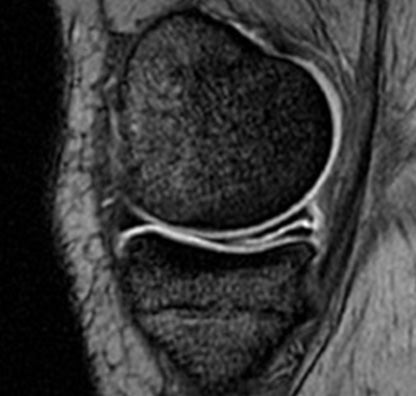

Could My Knee Pain Be a Meniscus Tear? Several conditions, including a meniscus tear, can cause knee pain. Symptoms of a meniscus tear may include catching or clicking sensations when...

Meniscus Tear